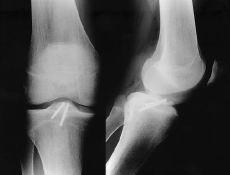

Las fracturas Tipo II, en las que no se consigue una reducción anatómica, deben tratarse quirúrgicamente mediante reducción y osteosíntesis.12,40 Todas las fracturas Tipos III, IV y V deben tratarse mediante reducción quirúrgica y osteosíntesis, habitualmente por artroscopia, empleando suturas, agujas o tornillos, recomendando una inmovilización postoperatoria de 3 semanas y descarga de 6 semanas (Fig. 1). No se recomienda la fijación transepifisaria debido al riesgo de provocar una lesión de la placa fisaria y una deformidad posterior en hiperextensión de la rodilla; para evitarlo algunos autores han recomendado realizar la sutura del fragmento al cuerno anterior del menisco medial o lateral.65

Figura 1. Niño de 14 años de edad con fractura de la espina tibial (Meyers y McKeever Grado III). A: Radiografías preoperatorias. B: Fijación artroscópica con dos tornillos de Whipple. C: Radiografía a las 10 semanas de evolución donde se aprecia consolidación de la fractura.